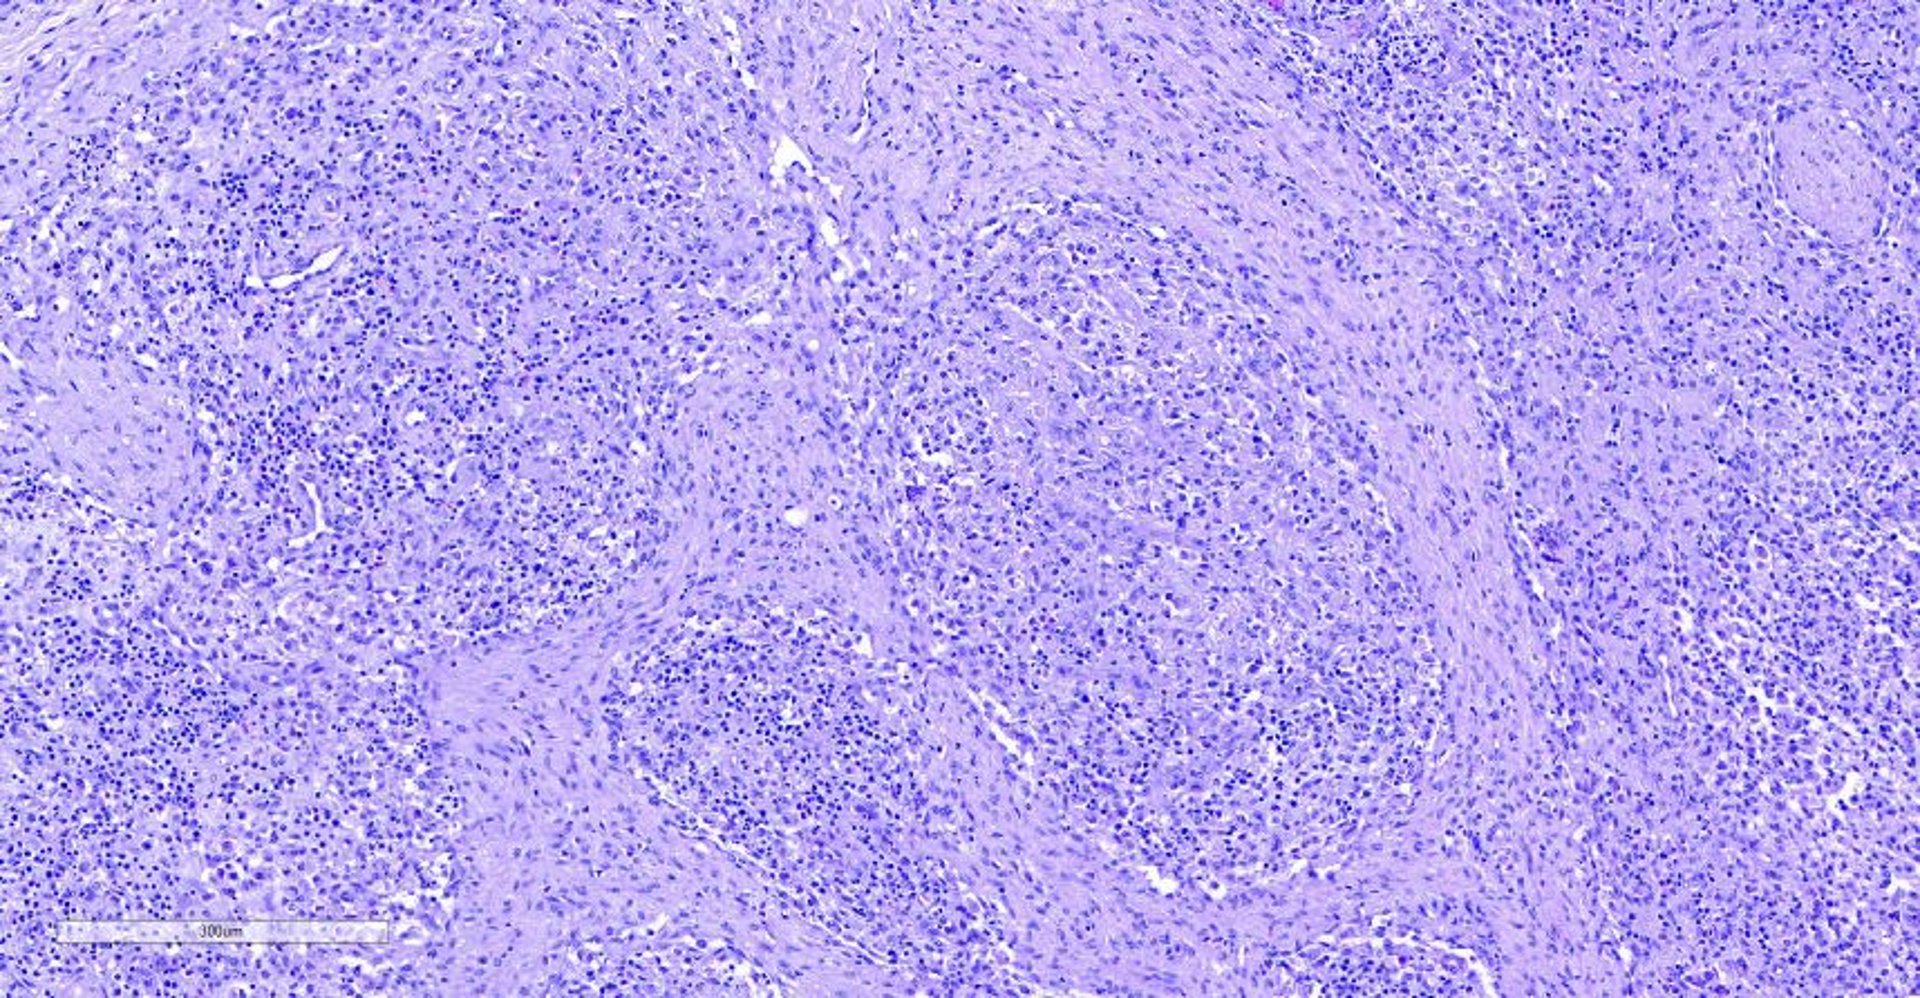

Histopathological lymphoid lesions are characteristic, showing lymphocytic depletion and granulomatous inflammation, sometimes with the presence of multinucleate giant cells and amphophilic botryoid intracytoplasmic inclusion bodies of different sizes, caused by the accumulation of PCV2 particles.

Because PCV2 and PCV3 are ubiquitous pathological agents, diagnosis of the diseases they cause must fulfil at least three criteria: clinical signs, histopathological lesions (see PCV2-SD photomicrograph), and in situ detection of the virus within lesions.

Courtesy of Dr. Joaquim Segalés.

Immunohistochemistry or in situ hybridization can be used to visualize specific viral antigens or genomes, respectively, within lesions (see PCV2 antigen detection image). Moderate to high amounts of virus are linked to clinical disease.